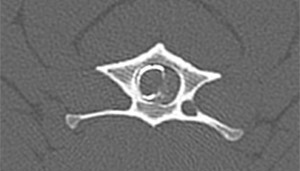

• Pruebas avanzadas de imagen

• Procedimientos quirúrgicos: patología discal, patologías congénitas, procesos traumáticos, neoplasias, ...